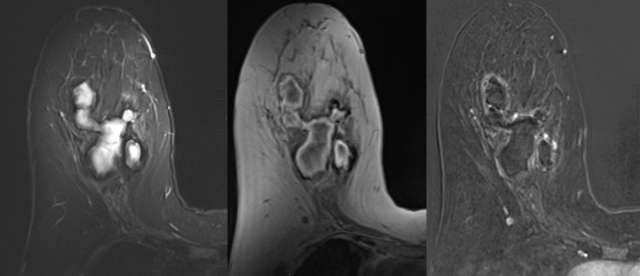

• MRI: Variable T1/T2 appearance depending on chronicity. High intensity unenhanced T1 appearance with fluid-fluid level (hematocrit level) is characteristic. May demonstrate low-signal intensity hemosiderin rim on T2, Figure 3.7

Case: Post-Surgical Fluid Collections Figure 3

Figure 3 - STIR, T1, and contrast enhanced digital subtraction MRI of the right breast 5 weeks following biopsy. STIR hyperintensity, T1 intrinsic hyperintensity, mild rim enhancement are characteristic of hematoma.